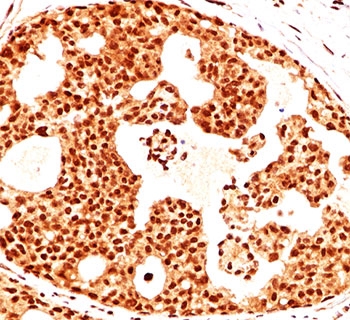

IHC testing of human ovarian cancer stained with Estrogen Receptor beta antibody (ERb455).

The antibody produces strong nuclear staining in ER beta positive tissues. In oncology, it is frequently applied to studies of breast and prostate cancer. ER beta expression has been associated with tumor suppression, contrasting with ER alpha, which promotes proliferation. Detection with this antibody therefore supports research into cancer progression and therapeutic strategies.